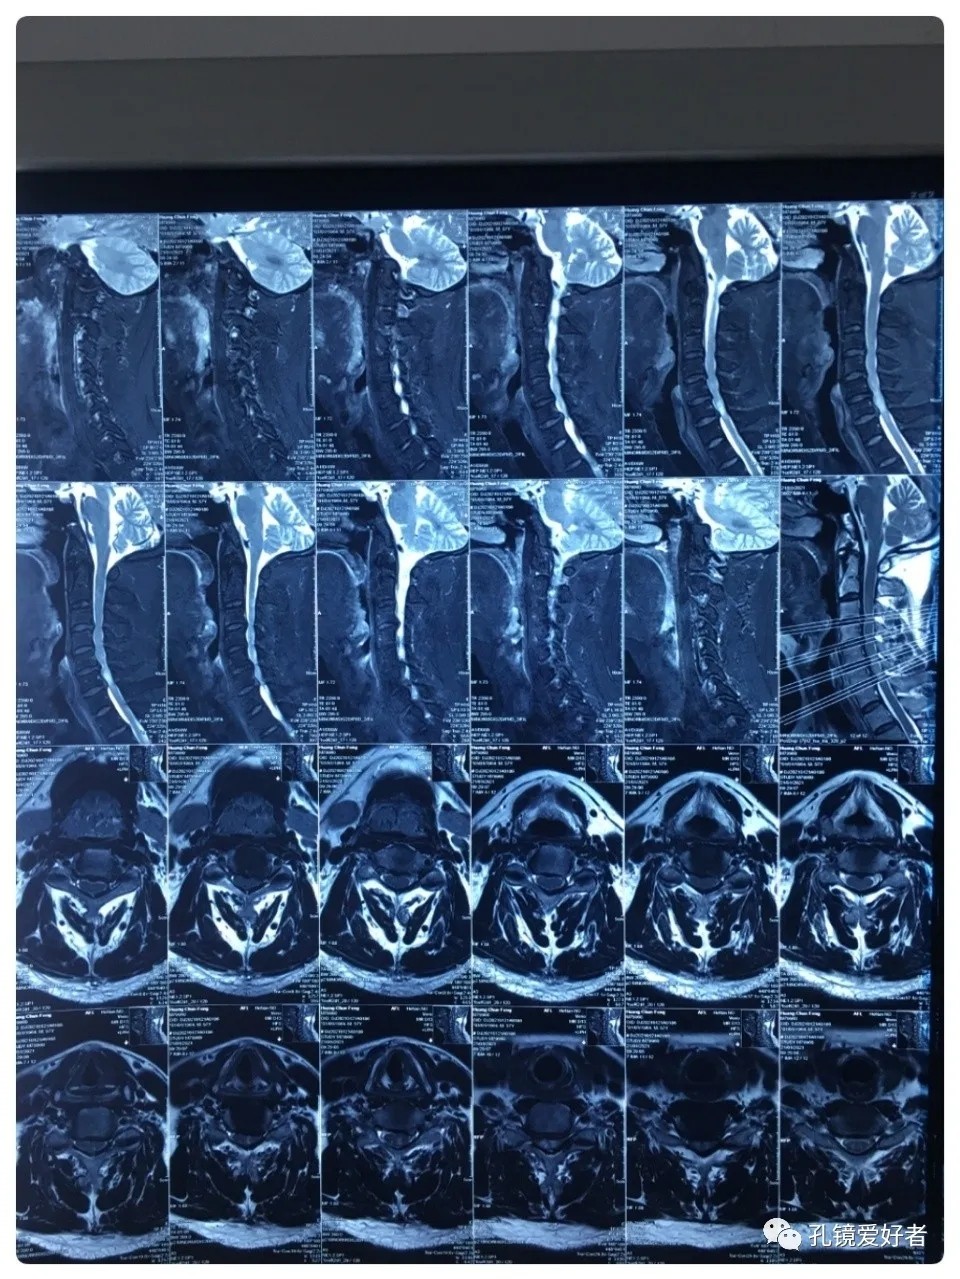

Plain MRI Scan

The patient's preoperative imaging data

The MRI shows that the cervical stenosis is on C3-4, C5-6 and C6-7. Considering the patient's clinical symptoms, C5-6 and C6-7 are the main affected segments. So it’s advised that the patient  undergo posterior cervical open-door laminoplasty. According to the patient, he had visited many hospitals before and received similar proposals of diagnosis and treatment- posterior cervical open-door laminoplasty. The reason he came to our hospital was that he wanted his surgery could be performed in a minimally invasive way. After considerable preoperative discussion with my colleagues and the patient, we decided to perform the minimally invasive endoscopic decompression for C5-6 and C6-7 double-segment stenosis through posterior approach (with the Delta system).